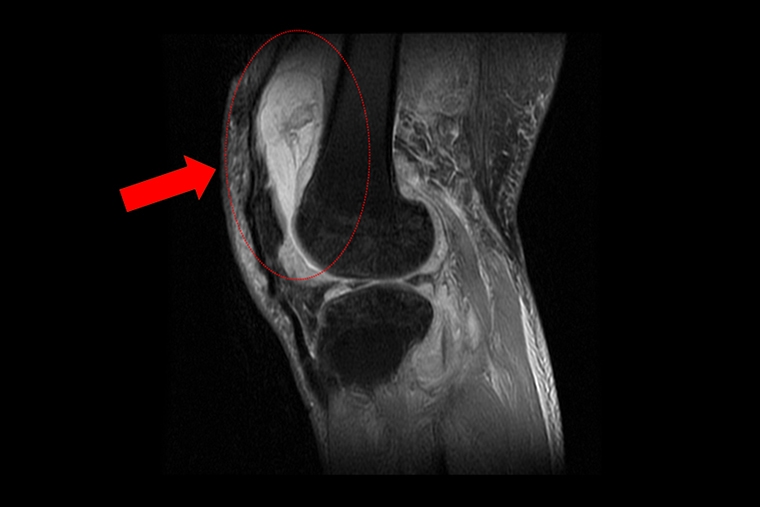

收治這名個案的台中慈濟醫院關節中心主任周立展表示,賴先生在就診時自認只是罹患退化性關節炎,但過去數月在服用止痛藥、抽取關節積水、熱敷復健後卻不見改善,症狀反而越來越嚴重,來院時膝蓋已明顯腫脹且無法彎曲。隨即安排抽取關節液化驗,發現其白血球數值雖偏高,但並非典型的細菌感染,懷疑有其他原因。於是便進一步安排個案住院,接受X光與磁振造影檢查,結果顯示其膝蓋內已有大量積液並化膿,屬於嚴重關節感染。

為避免病情惡化,院方立即安排個案接受微創關節鏡清創手術,並將檢體送往病理化驗,結果顯示感染源為結核分枝桿菌,證實膝關節問題並非單純退化性變化。隨後,周立展與感染科及胸腔科醫師共同會診,並在個案痰液中培養出結核菌,確認為「肺結核合併肺外感染」。而結核菌最初是在肺部感染,透過血液或淋巴傳播至膝關節。個案在住院期間接受抗結核藥物治療,1周後膝蓋腫脹明顯消退,已能正常彎曲行走。出院後仍需持續服藥至少9個月,並定期回門診追蹤,以確保結核菌完全清除。